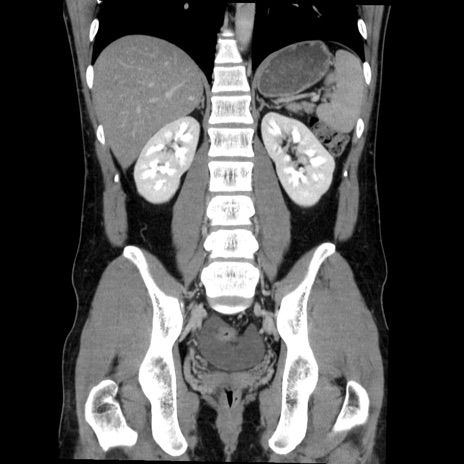

症例36(冠状断像)

【症例】20歳代 男性

【主訴】心窩部痛

【現病歴】今朝より上腹部痛あり。一旦軽快していたが再度出現したため救急要請。昨日夕に白身の魚を含む刺身を食べた。

【身体所見】BP 136/89mmHg、HR 74/min、BT 37.0℃、腹部:膨満、軟、心窩部に圧痛あり。反跳痛なし、筋性防御なし、腸雑音やや亢進あり。

【データ】WBC 17700、CRP 0.48